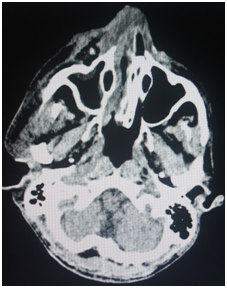

The patient was started on intravenous antibiotics which included Piperacillin 2.5 gms and Linezolid 600mg 12 hourly. A combination of Injection Human Actrapid and Insultard were used for his glyceamic control. However, he did not respond to the therapy and the area was severely infected. CT scan revealed the presence of a diffuse soft tissue swelling superficial to the right parotid space extending to the right buccal space with increased density and streakiness of sub cutaneous fat consistent with inflammation. The underlying bone seemed to be unaffected (Figure 3).

Figure 3 Underlying bone seemed to be unaffected.